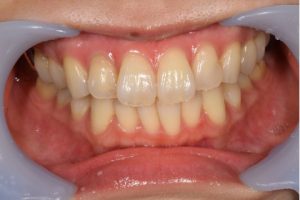

症例写真(治療前)

担当医師所見

治療前:

八重歯が目立ちます。また銀歯もおおく、見た目が気になります。虫歯も散見できます。

症例写真(治療後)

矯正装置をつけています。だんだん八重歯が動いてきているのがわかります。今回のケースでは、抜歯を行わずに矯正ができました。

治療後:

矯正治療と虫歯の治療すべて終わったときの写真になります。見た目も最初の頃とは全く違いますし、お口の中もすごく綺麗です。

治療

方針

まずは虫歯の治療を行い、被せ物をする部分は仮歯をいれて矯正を行う。矯正終了後、仮歯の部分を最終的な被せ物に変えていく。また気になっていた銀歯もセラミックに変えて終了となった。

内容

セラミックインレー、オールセラミックプレミアム、矯正